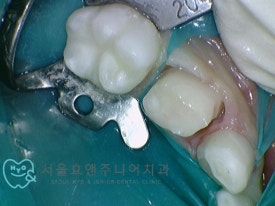

다음은 치아의 양 옆 사이가 썩어 가운데 낀 치아를 크라운한 케이스입니다.

치아의 양쪽에 사이충치가 있습니다.

양쪽 치아 레진치료 후, 가운데 치아 크라운치료 들어갑니다.삭제량이 크지 않아 신경치료 없이도 치료하였으며 잇몸 아래로 기구를 넣어 다듬는데도 잇몸에 출혈이 나지 않습니다.(잇몸이 크게 다치치 않습니다.)

양쪽 치아 레진치료 후, 가운데 치아 크라운치료 들어갑니다.삭제량이 크지 않아 신경치료 없이도 치료하였으며 잇몸 아래로 기구를 넣어 다듬는데도 잇몸에 출혈이 나지 않습니다.

(잇몸이 크게 다치치 않습니다.)